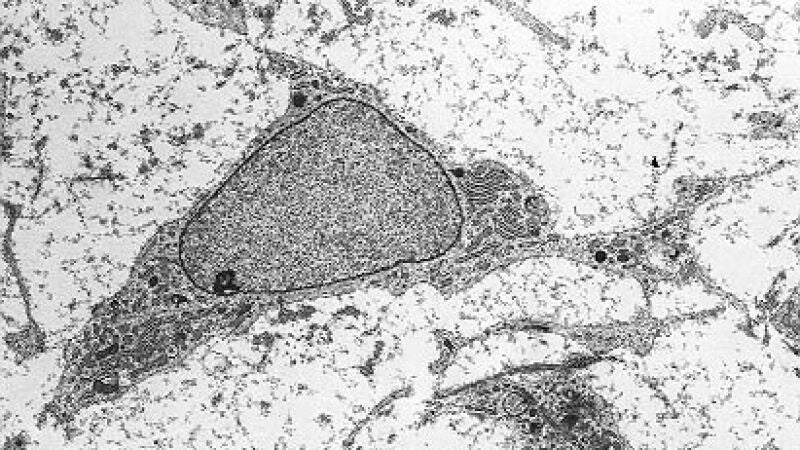

Estudios previos en animales y humanos habían sugerido el potencial de las células madre mesenquimales de la médula ósea, también conocidas como células estromales o MSC –por sus siglas en inglés– en el tratamiento del lupus, ya que se considera que la enfermedad puede ser producto de una alteración en el tejido mesenquimal, aquel que da lugar, por ejemplo, a huesos, músculos o cartílagos.

La terapia, consistente en la introducción por vía endovenosa de 90 millones de células madre mesenquimales, se administró cuando los pacientes se encontraban en momento de brote y no respondían al tratamiento previo. Después, se realizó seguimiento de los pacientes midiendo diferentes parámetros, específicos del riñón y generales, tras 1, 3, 6 y 9 meses del tratamiento.